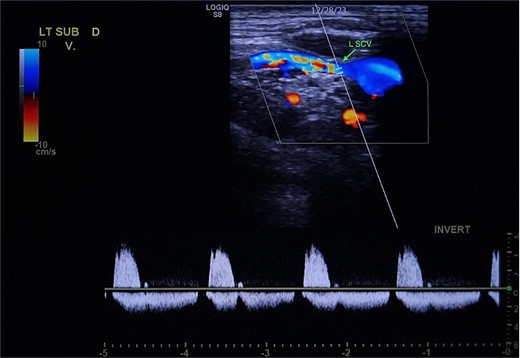

Demonstration of arterial waveform in the left subclavian vein on Duplex ultrasound (green arrow: left subclavian vein).